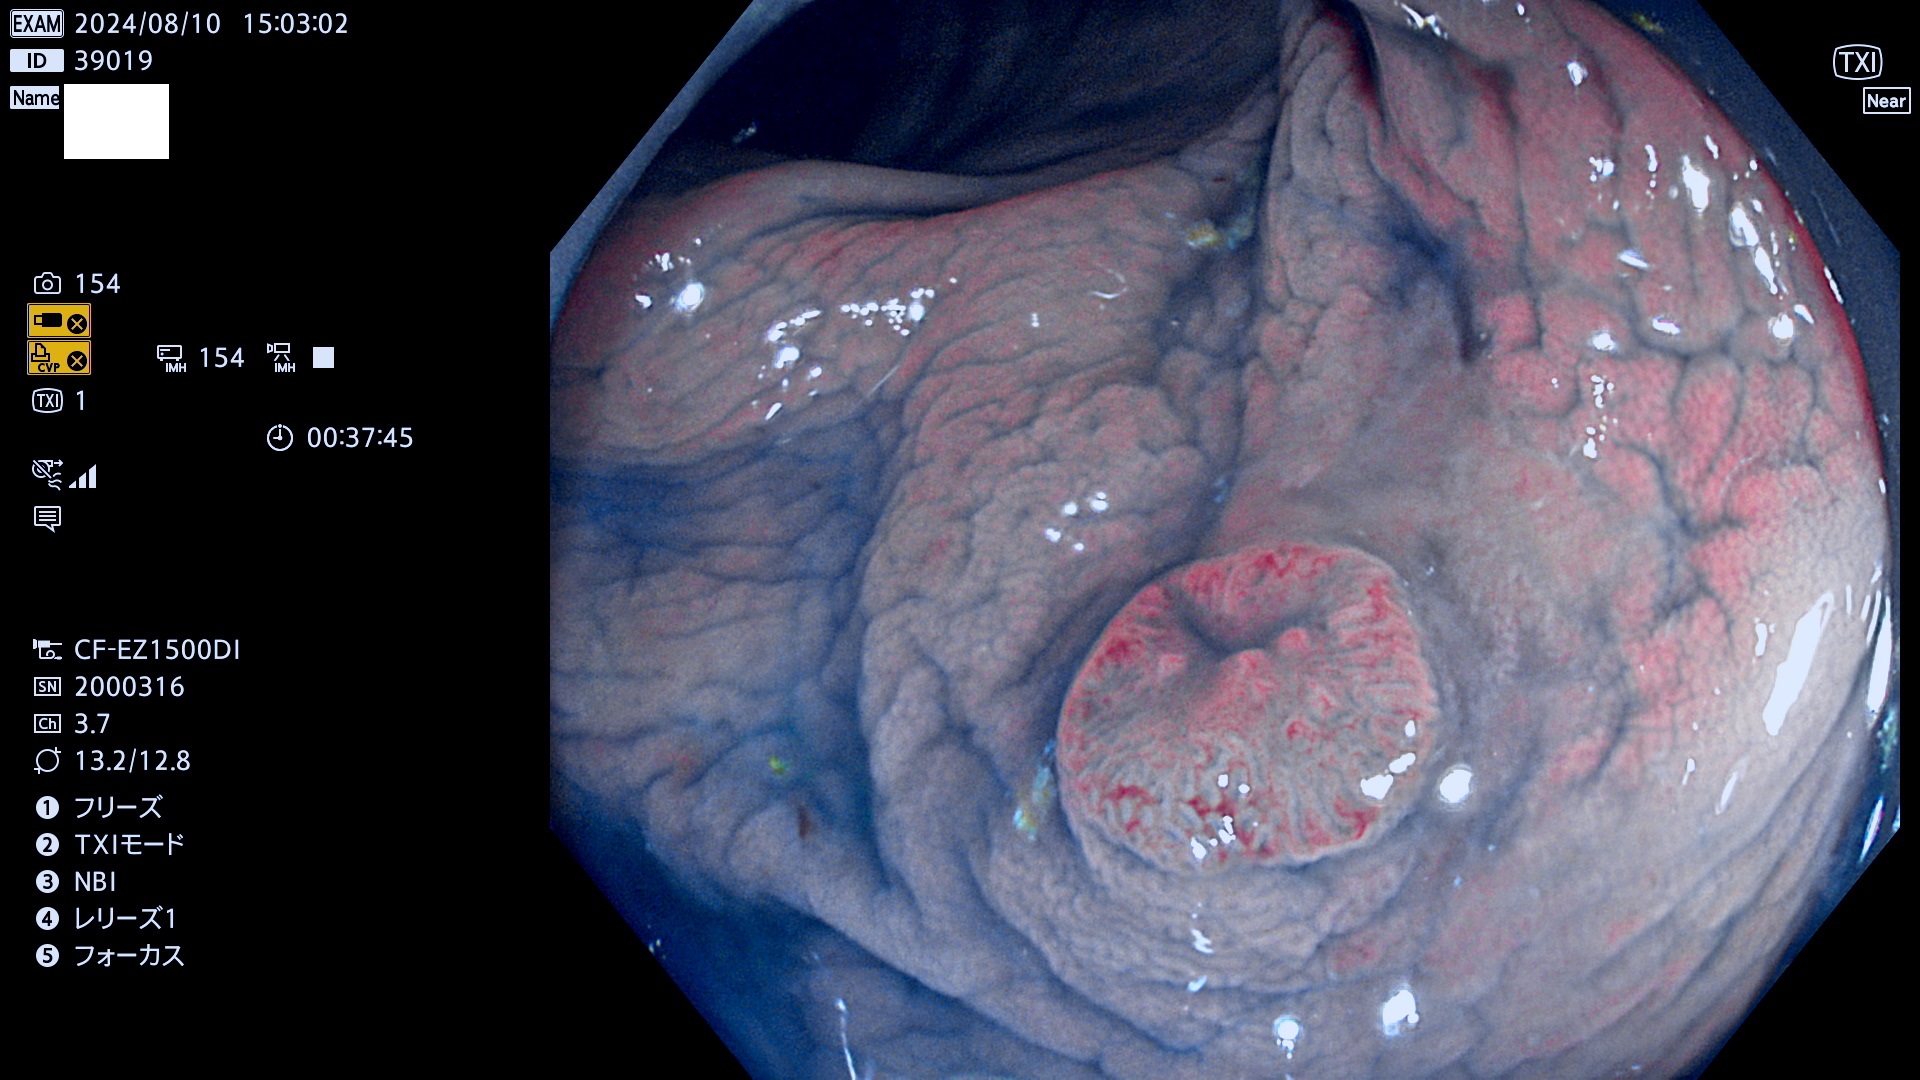

完全に平坦な物をUb、陥凹している物をUcと呼びます。最も発見が難しく危険な病変です。

抽出の対象期間 2024年8月8日〜8月11の4日間(30件の検査)11件 (11/30=35%)